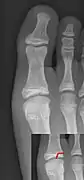

- Salter–Harris III fracture of big toe proximal phalanx.

- Salter–Harris IV fracture of big toe proximal phalanx.